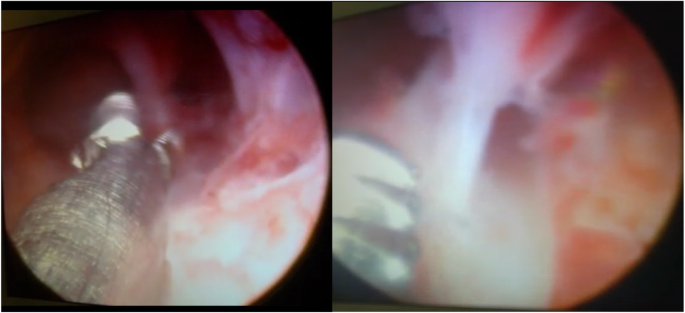

On the 20th day of the patient’s menstrual cycle, she was administered GnRH agonist 3.75 mg intramuscularly. Sixteen days after the injection (on the fourth day of her next menstrual cycle), ultrasound monitoring of the endometrium and hysteroscopy were performed. According to ultrasound monitoring, her endometrial thickness was 0.2 cm, single-layered, and its structure was not visualized in the middle third of the uterine cavity. Diagnostic hysteroscopy, removal of intrauterine adhesions in the middle third of the uterine cavity (Fig. 3), and submucosal administration of cultured endometrial MSCs at a dose of 20 million cells were performed.